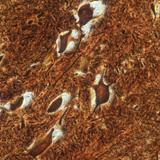

Нервни клетки в гръбначен мозък (говедо)

100х увеличение